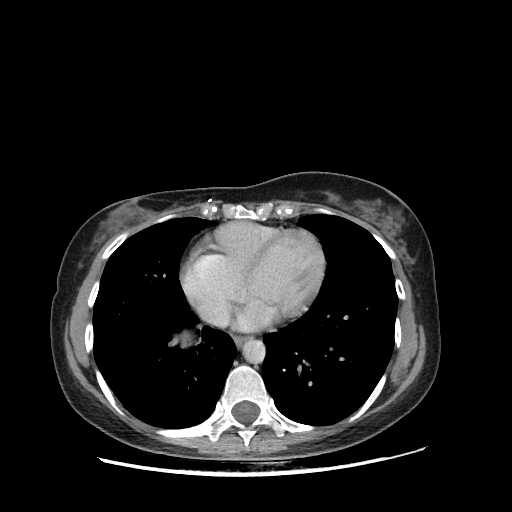

Generated VENOUS CT scan (A→B translation)

Full window (WL 1023.5, WW 4095 β†’ Low βˆ’1024, High +3071)

Lung window (WL -600, WW 1500 β†’ Low βˆ’1350, High +150)

Mediastinum window (WL 40, WW 400 β†’ Low βˆ’160, High +240)